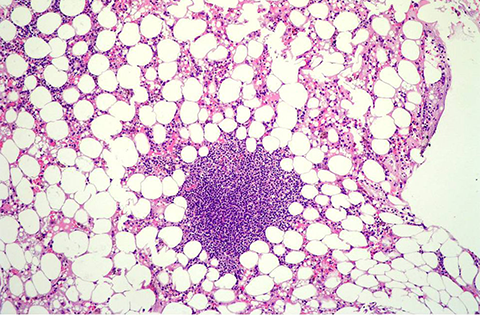

Anemia aplásica

Fallo de la médula ósea para producir células sanguíneas